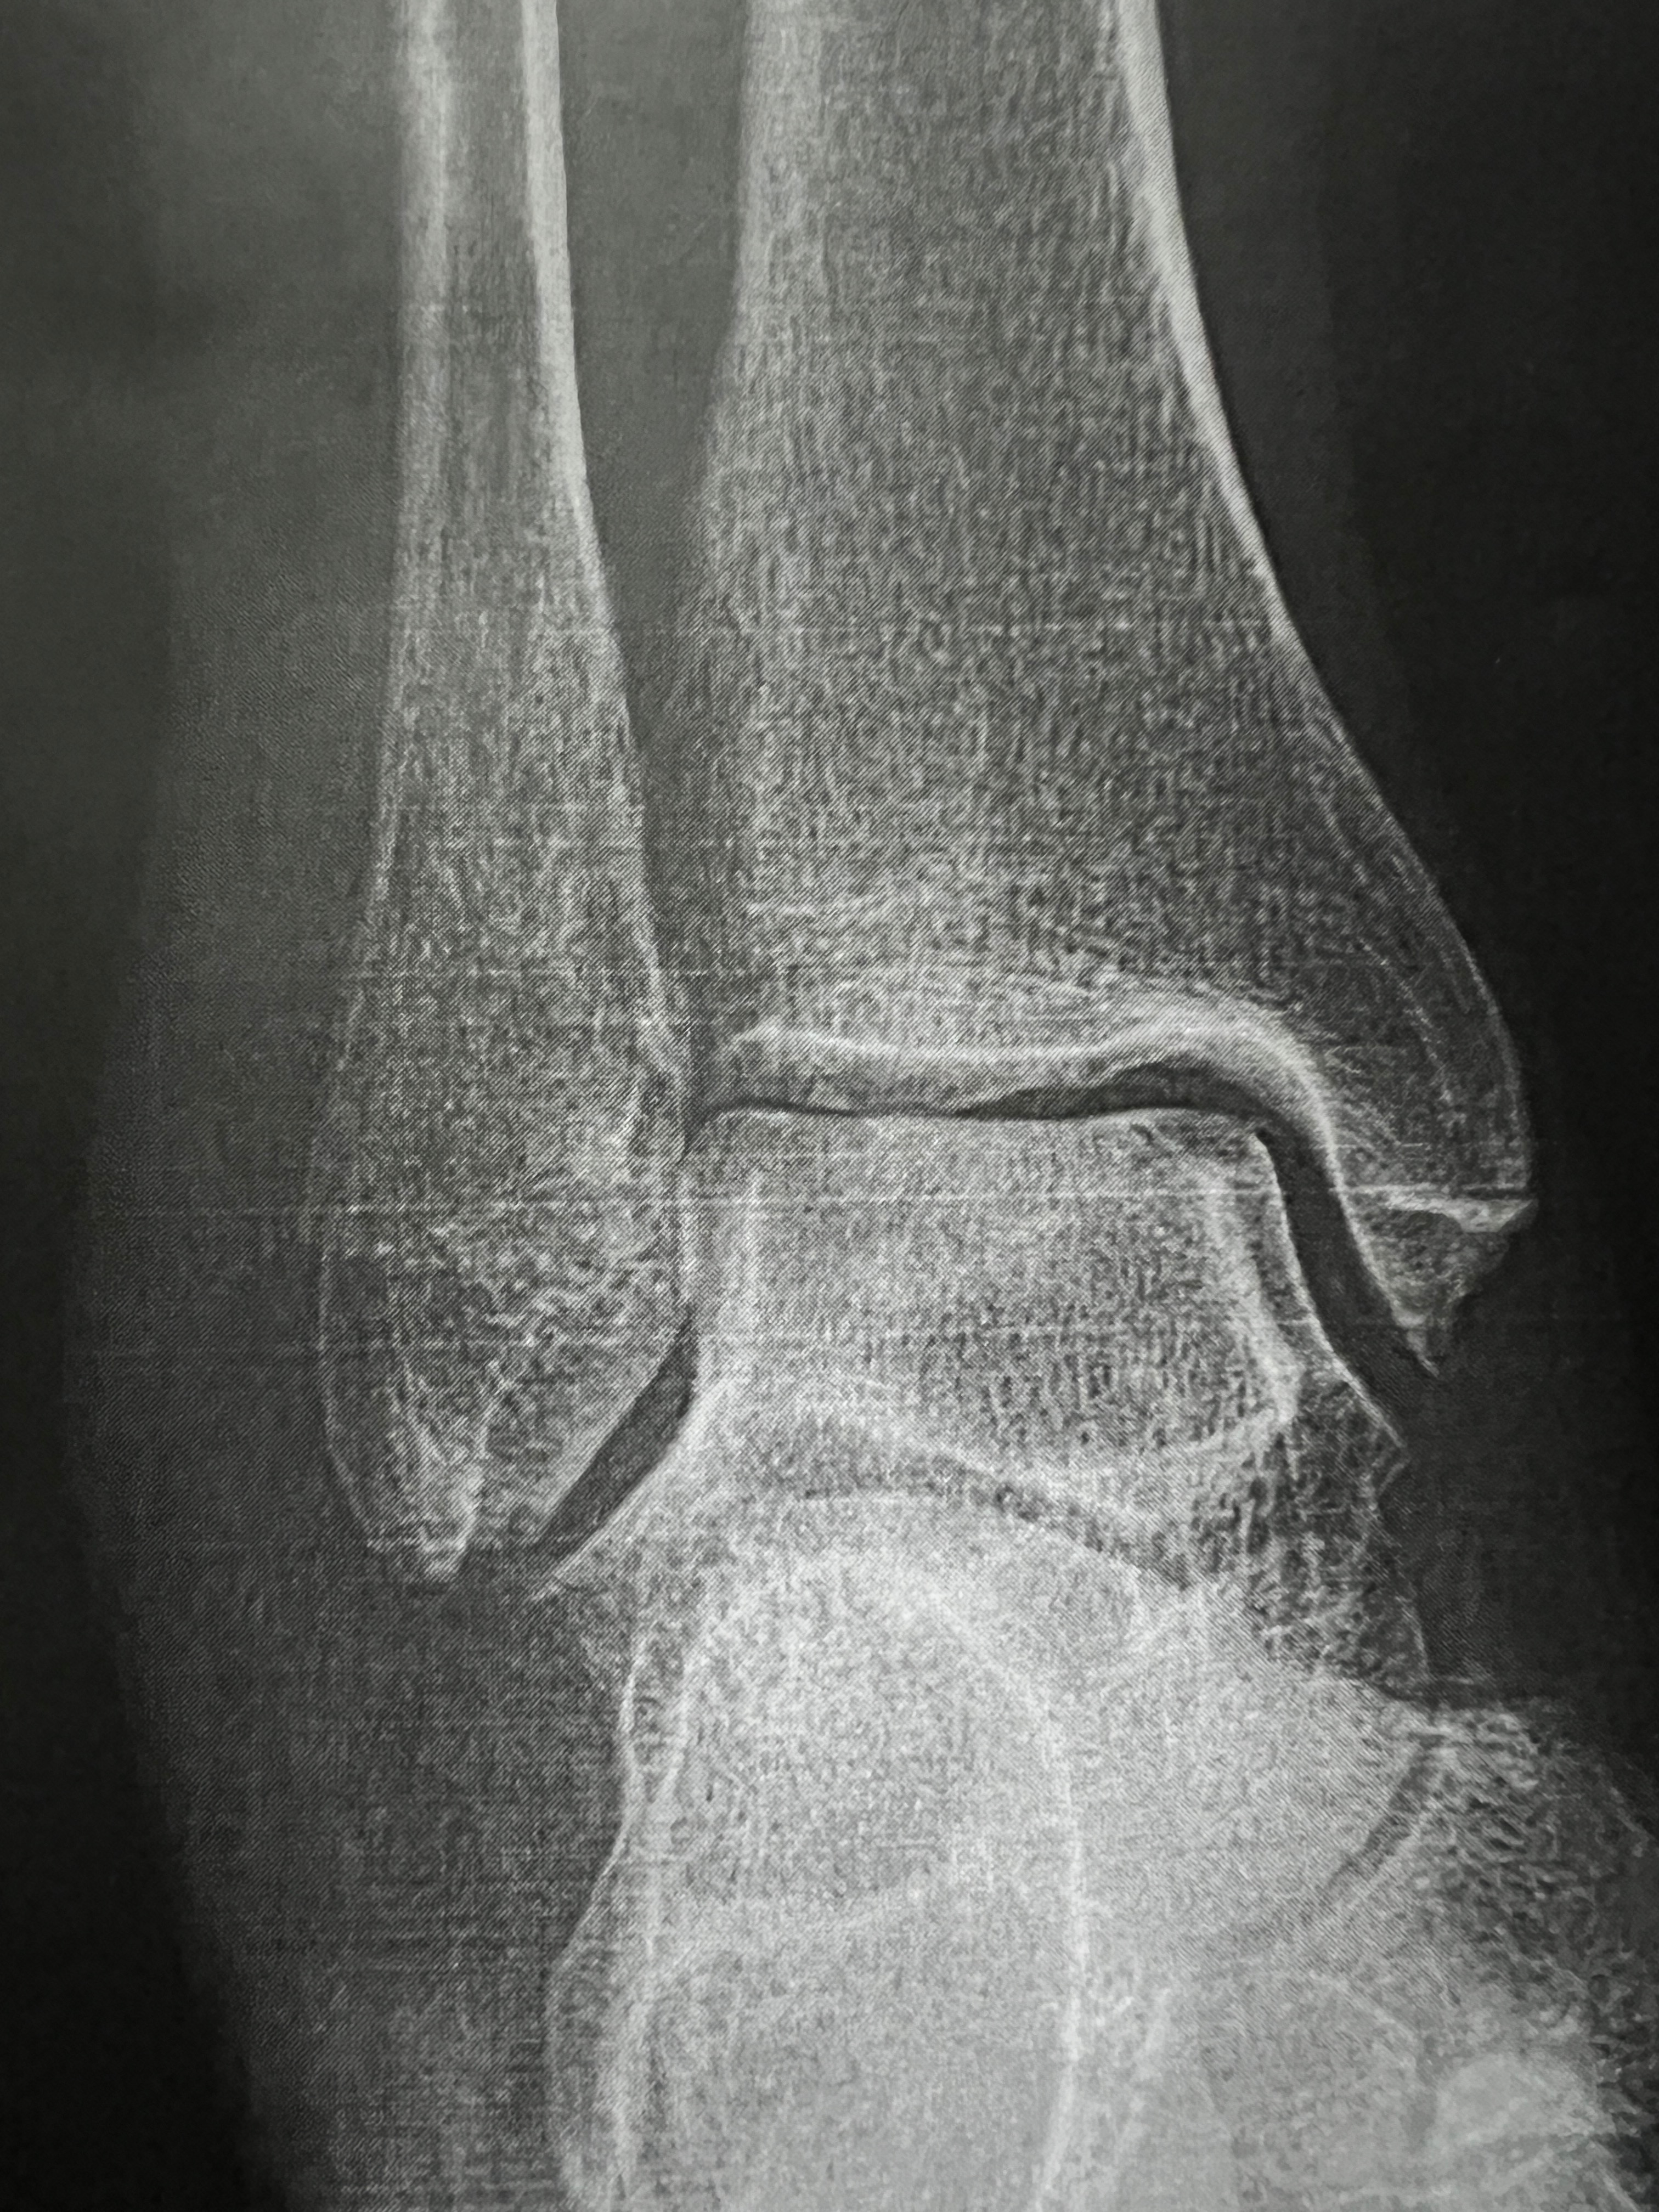

- Broke my ankle trying to be in shape.

- One month down & two to go in the cast.

- Next X-ray scheduled for end of December.